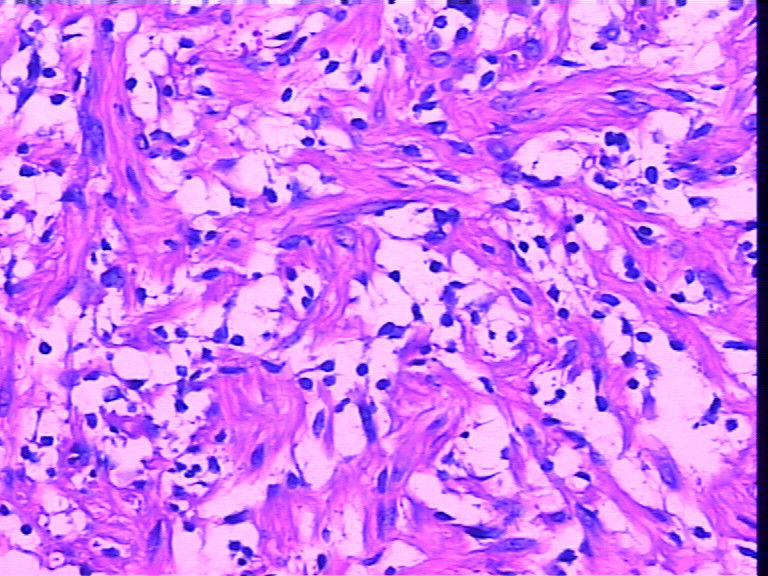

腹壁一个包块,大小4cmx2cmx2cm,椭圆形,有菲薄包膜,淡黄色,切面淡黄色半透明,质地偏韧。

是女性患者,19岁。考虑为神经方面肿瘤,等着病人过来加做免疫组化。

感觉首先是孤纤和神经纤维瘤(图3很像,但是有包膜,神经鞘需要考虑)鉴别。

神经纤维瘤